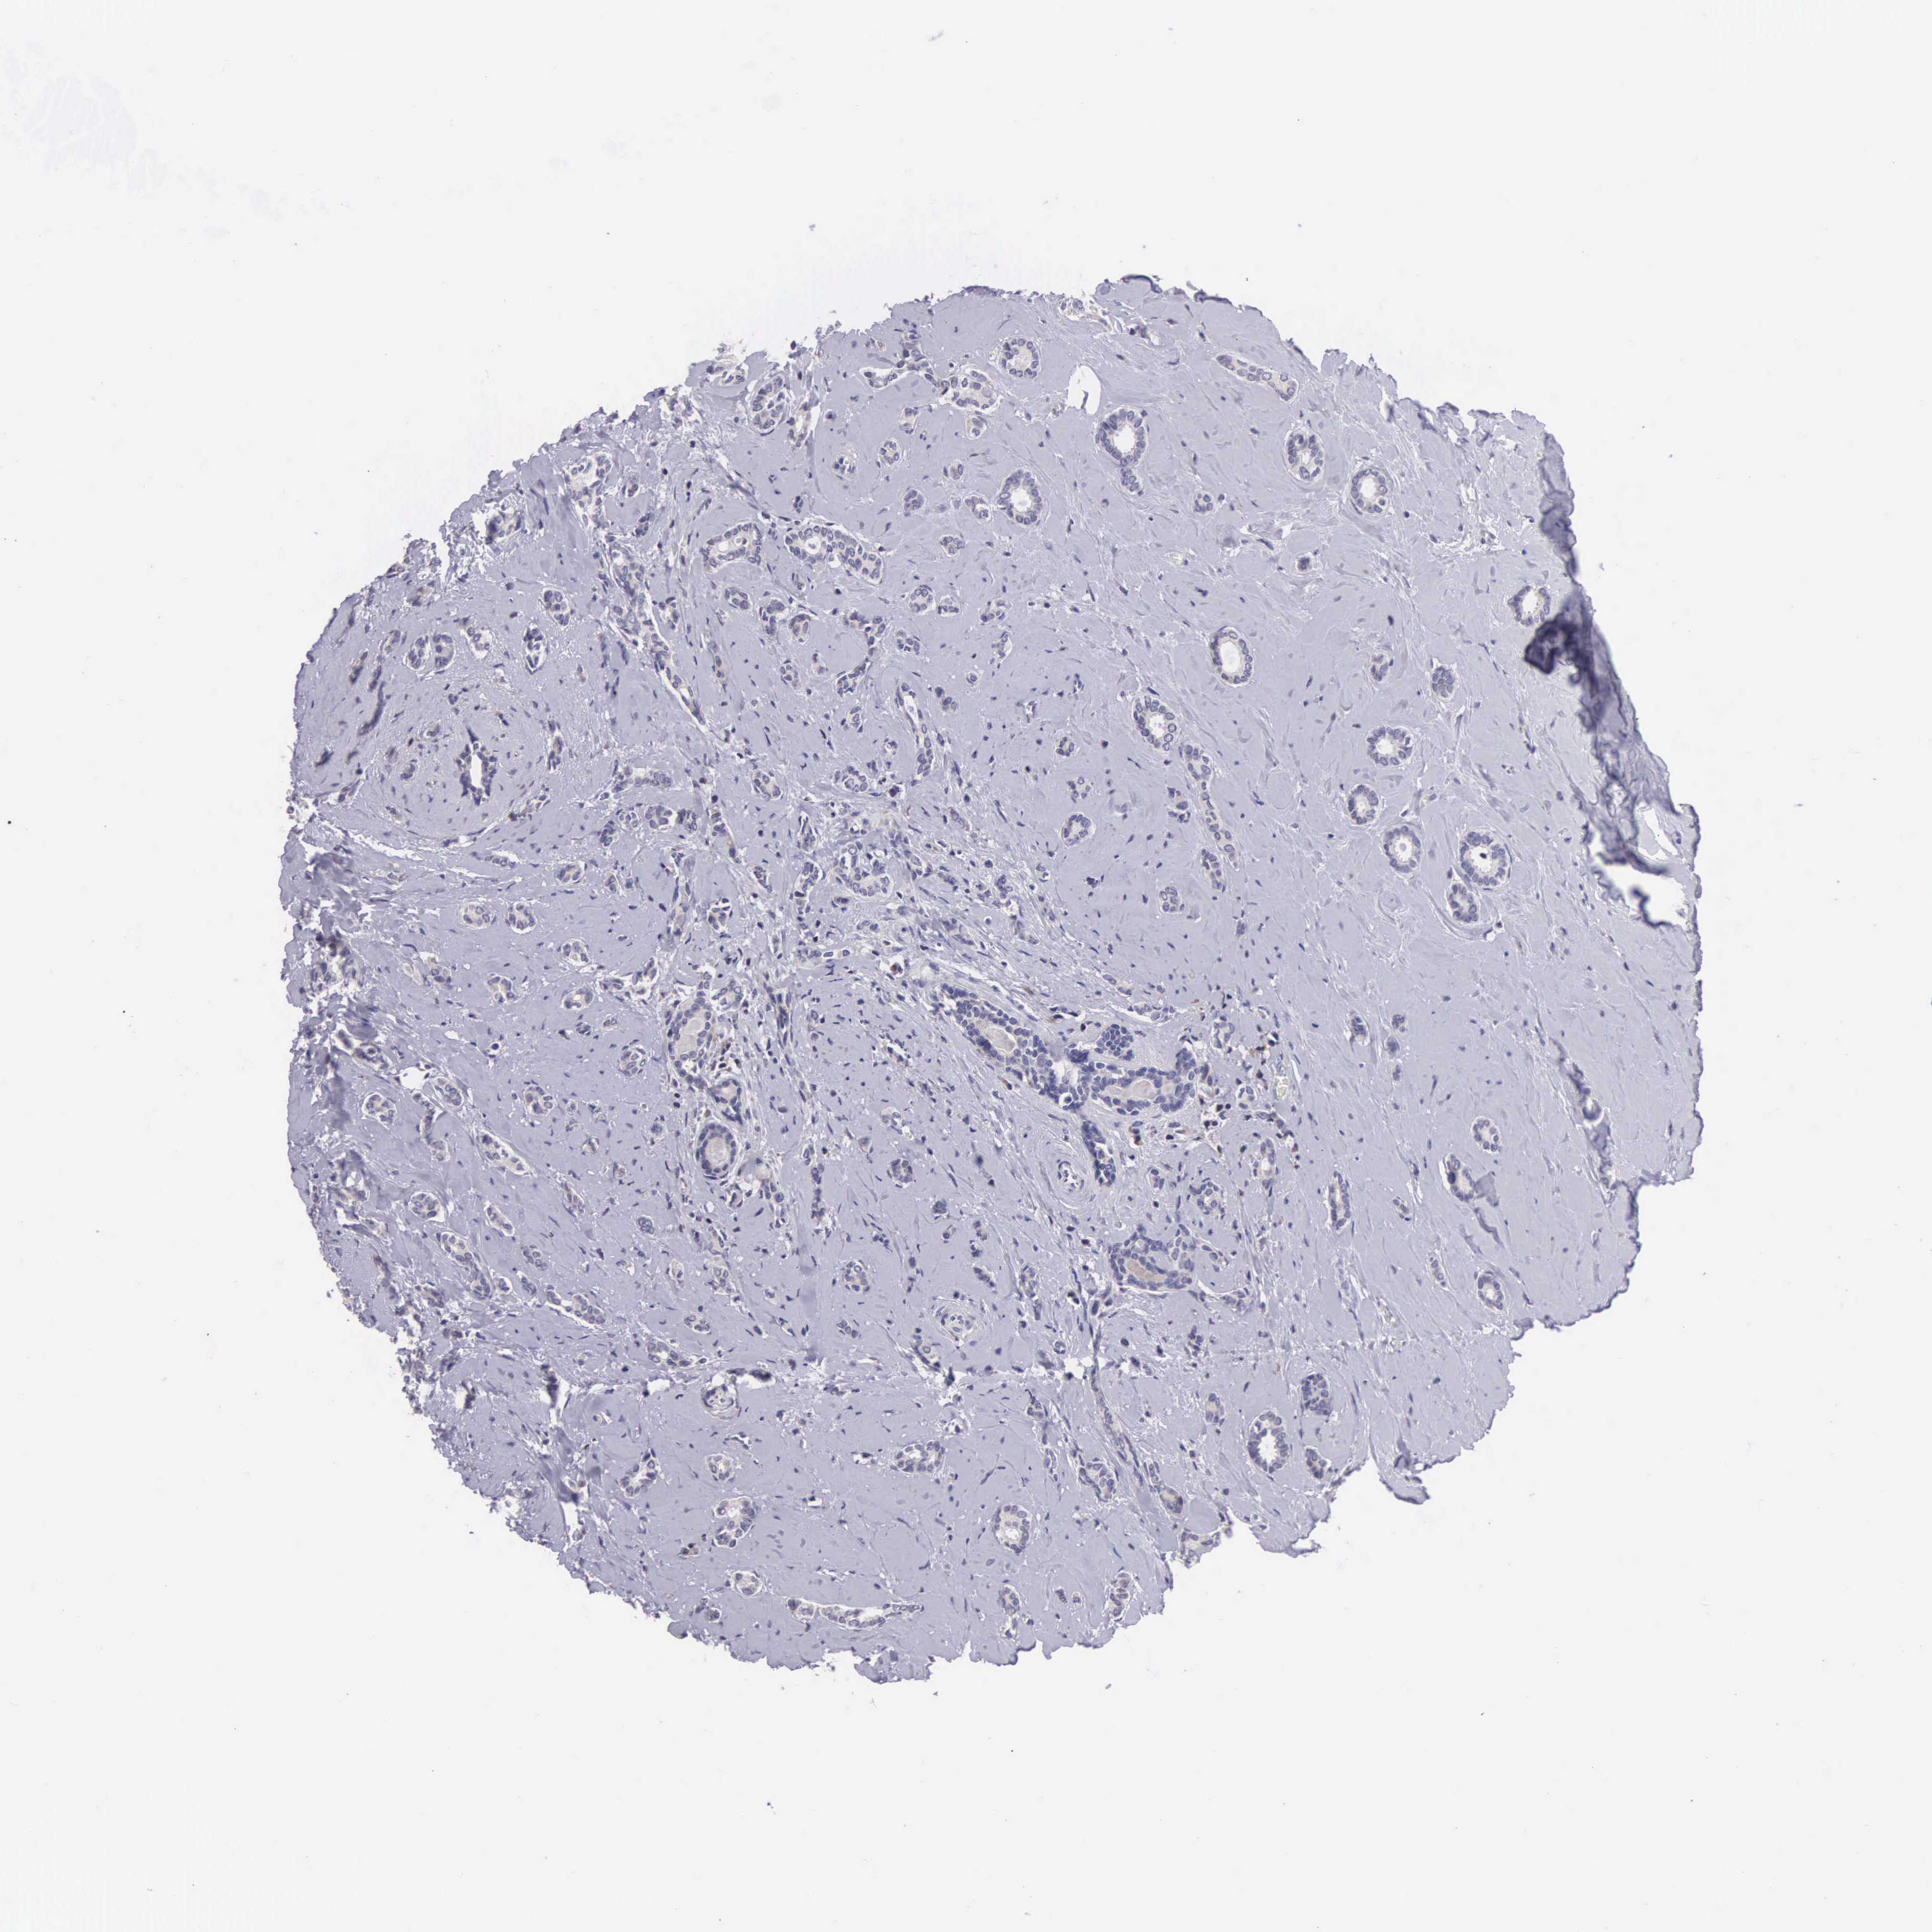

CANCER BREAST CANCER Show tissue menu

BRCA TCGA BRCA VALIDATION PROTEIN EXPRESSION

ANTIBODIES

AND

VALIDATION